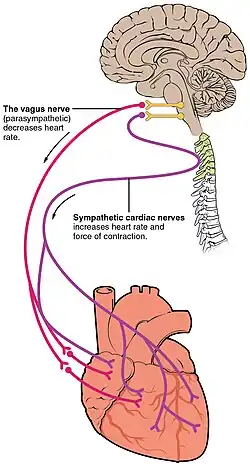

While heart rhythm is regulated entirely by the sinoatrial node under normal conditions, heart rate is regulated by sympathetic and parasympathetic input to the sinoatrial node. The accelerans nerve provides sympathetic input to the heart by releasing norepinephrine onto the cells of the sinoatrial node (SA node), and the vagus nerve provides parasympathetic input to the heart by releasing acetylcholine onto sinoatrial node cells. Therefore, stimulation of the accelerans nerve increases heart rate, while stimulation of the vagus nerve decreases it.[6]

The heart rate is rhythmically generated by the sinoatrial node. It is also influenced by central factors through sympathetic and parasympathetic nerves.[11] Nervous influence over the heart rate is centralized within the two paired cardiovascular centres of the medulla oblongata. The cardioaccelerator regions stimulate activity via sympathetic stimulation of the cardioaccelerator nerves, and the cardioinhibitory centers decrease heart activity via parasympathetic stimulation as one component of the vagus nerve. During rest, both centers provide slight stimulation to the heart, contributing to autonomic tone. This is a similar concept to tone in skeletal muscles. Normally, vagal stimulation predominates as, left unregulated, the SA node would initiate a sinus rhythm of approximately 100 bpm.[12]

Both sympathetic and parasympathetic stimuli flow through the paired cardiac plexus near the base of the heart. The cardioaccelerator center also sends additional fibers, forming the cardiac nerves via sympathetic ganglia (the cervical ganglia plus superior thoracic ganglia T1–T4) to both the SA and AV nodes, plus additional fibers to the atria and ventricles. The ventricles are more richly innervated by sympathetic fibers than parasympathetic fibers. Sympathetic stimulation causes the release of the neurotransmitter norepinephrine (also known as noradrenaline) at the neuromuscular junction of the cardiac nerves. This shortens the repolarization period, thus speeding the rate of depolarization and contraction, which results in an increased heartrate. It opens chemical or ligand-gated sodium and calcium ion channels, allowing an influx of positively charged ions.[12]

Parasympathetic stimulation originates from the cardioinhibitory region of the brain[13] with impulses traveling via the vagus nerve (cranial nerve X). The vagus nerve sends branches to both the SA and AV nodes, and to portions of both the atria and ventricles. Parasympathetic stimulation releases the neurotransmitter acetylcholine (ACh) at the neuromuscular junction. ACh slows HR by opening chemical- or ligand-gated potassium ion channels to slow the rate of spontaneous depolarization, which extends repolarization and increases the time before the next spontaneous depolarization occurs. Without any nervous stimulation, the SA node would establish a sinus rhythm of approximately 100 bpm. Since resting rates are considerably less than this, it becomes evident that parasympathetic stimulation normally slows HR. This is similar to an individual driving a car with one foot on the brake pedal. To speed up, one need merely remove one's foot from the brake and let the engine increase speed. In the case of the heart, decreasing parasympathetic stimulation decreases the release of ACh, which allows HR to increase up to approximately 100 bpm. Any increases beyond this rate would require sympathetic stimulation.[12]